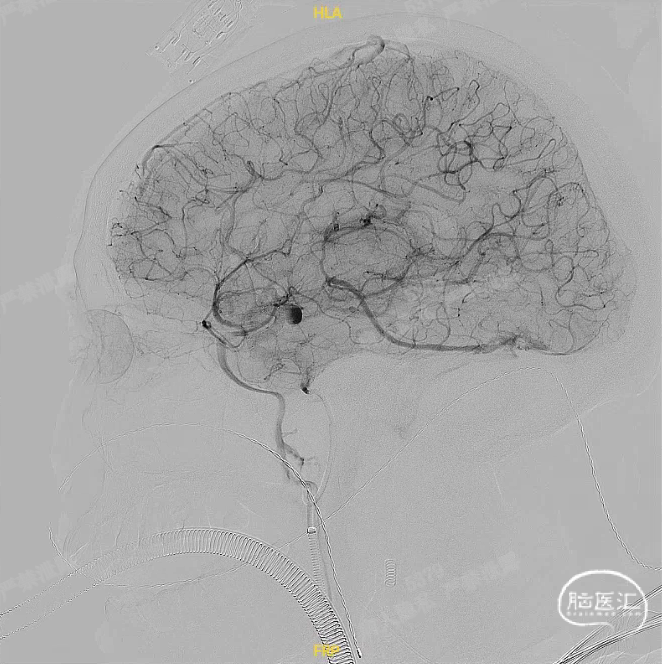

正、侧位造影观察,载瘤动脉通畅、支架贴壁良好、动脉瘤内造影剂滞留。

工作角度、侧位造影CT复查结果观察,载瘤动脉通畅、支架贴壁良好、动脉瘤内造影剂滞留,颅内未见明显异常。